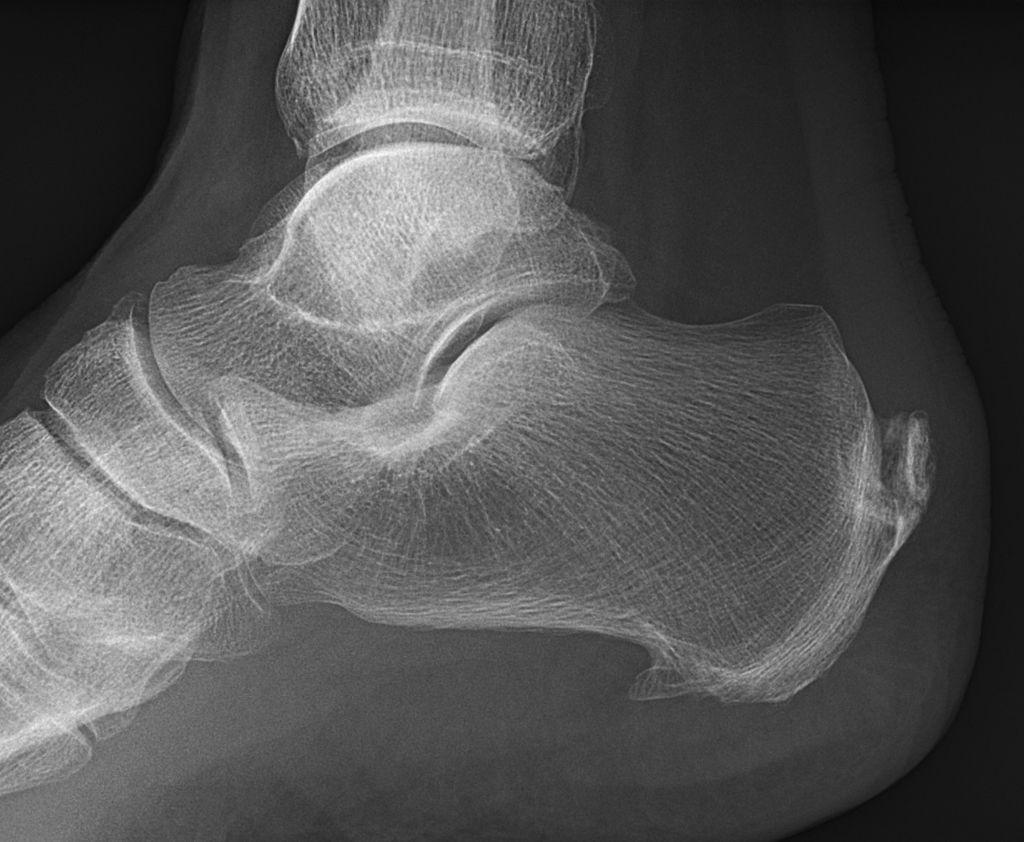

4. 骨赘形成

骨质增生是指人体骨骼边缘形成的骨性增生物,可能与关节过度劳损、体重超重、关节异常受力等原因有关。

骨赘通常出现于关节两端,或者活动度较大的脊柱骨边缘。一般好发于活动较频繁的关节,由于这些关节长时间反复使用,容易发生磨损和退化。 骨赘最常见于膝、髋、腰椎、颈椎、脚跟、手指和肘等部位。骨赘也可叫做骨质增生、骨刺。

没有症状的骨赘无需治疗 ,产生症状的骨赘主要有保守和手术两种治疗方法。骨赘 通常不需要手术治疗,只有在产生严重症状 (例如腰椎骨赘卡压、刺激神经产生疼痛)的时候, 才考虑手术治疗 。保守治疗主要是缓解疼痛、改善局部血液循环,减轻炎症,方法有休息、药物、理疗、康复锻炼等。